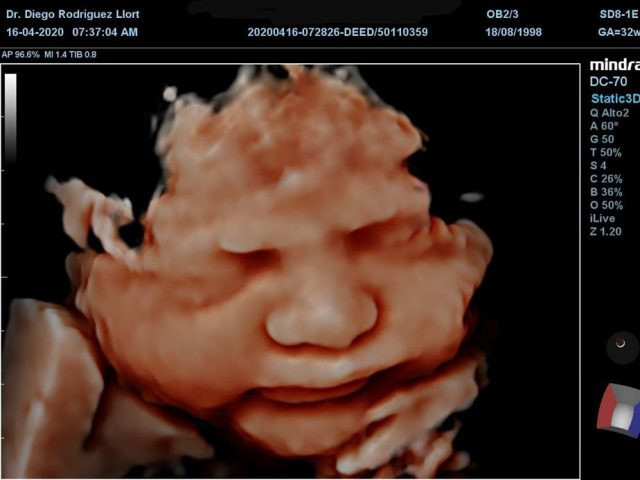

• Ultrasonido 3D y 4D: Las ecografías en tres dimensiones y cuatro dimensiones permiten ver de forma más clara al bebé, otorgándole volumen y movilidad en el 4D.

• Ultrasonido 5D: La ecografía 5D es capaz de realizar una reconstrucción más definida y realista del feto. La nueva generación de ecógrafos de alta resolución incrementa de manera decisiva la capacidad diagnóstica y la detección de malformaciones fetales.